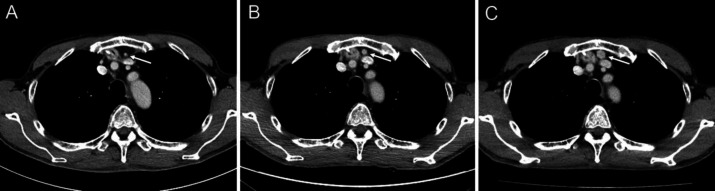

Splenosis occurs as a result of autotransplantation of splenic tissue following splenic injury or splenectomy. A 56-year-old man with esophageal cancer underwent thoracoscopic-assisted subtotal esophagectomy accompanied by three-field lymph node dissection, and retrosternal gastric tube reconstruction. The spleen was injured during the surgery and was removed. A retrosternal nodule of 12 mm in diameter was detected near the reconstructed gastric tube on computed tomography (CT) performed 3 years and 6 months postoperatively. Retrospectively, the nodule was observed in the same area on early postoperative CT and gradually increased in size. No accessory spleen was identified on the preoperative CT. Splenosis was suspected, and 99mTc-Sn-colloid single photon emission computed tomography (SPECT)/CT was performed. It revealed intense uptake in the retrosternal nodule, consistent with the diagnosis of thoracic splenosis. Subsequently, the patient has been under observation without treatment. 99mTc-labeled colloid SPECT/CT allowed confident diagnosis of thoracic splenosis following esophageal cancer surgery. This examination is considered valuable for the evaluation of ectopic splenic tissue.